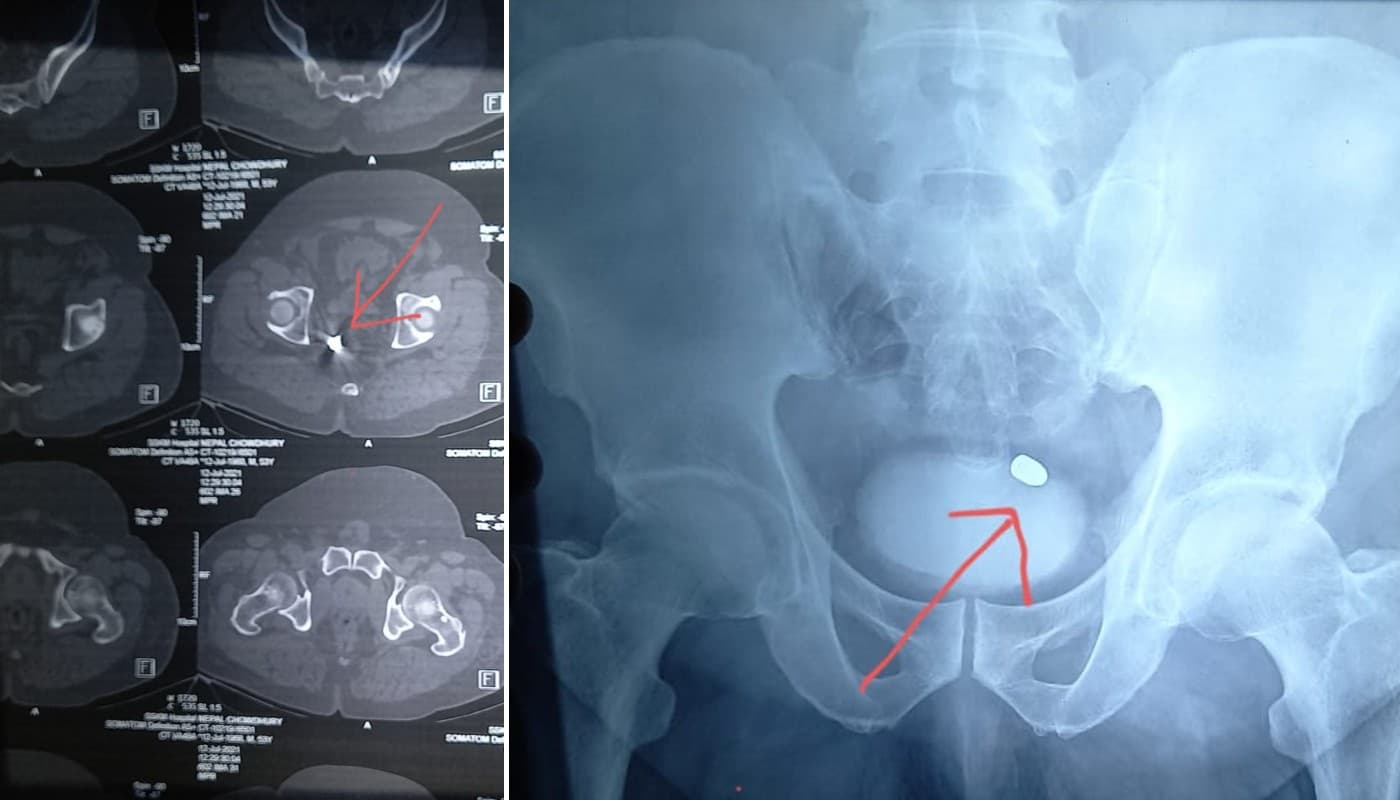

कोलकाता (जे कुंदन): पश्चिम बंगाल की राजधानी कोलकाता स्थित एसएसकेएम अस्पताल के डॉक्टरों ने मालदा के एक प्रमोटर की जान बचा ली. करीब चार घंटे तक चले इस ऑपरेशन में डॉक्टरों ने जोखिम लेते हुए मूत्राशय और मलाशय के बीच फंसी गोली को सफलतापूर्वक निकाल दिया.

डॉक्टरों के मुताबिक, मरीज का वजन 140 किलो होने के कारण ऑपरेशन बहुत जटिल था. ओपन सर्जरी करने से मरीज की जान जा सकती थी. इसलिए डॉक्टरों ने लेप्रोस्कोपिक सर्जरी करने का फैसला किया. सी-आर्म मशीन से एक्स-रे कर गोली को पहले लोकेट किया गया.

किडनी व लीवर को छूते हुए गोली मूत्राशय और मलाशय के बीच फंस गयी थी. इसे निकालने के लिए जनरल सर्जरी विभाग के तीन डॉक्टरों की टीम बनी. डॉ सिराज अहमद, डॉ शमिता चट्टोपाध्याय व डॉ प्रीतिन बेड़ा ने ऑपरेशन का जिम्मा संभाला और चार घंटे के प्रयास के बाद गोली निकालने में सफल रहे.

https://www.youtube.com/watch?v=9C2Yk1DW9xYउल्लेखनीय है कि मालदा के इंग्लिश बाजार इलाके में प्रमोटिंग विवाद को लेकर नेपाल चौधरी को प्वाइंट ब्लैंक रेंज से गोली मार दी गयी थी. मोटापा के कारण उनके पेट में चर्बी बहुत था. इसलिए गोली शरीर के अंदर फंस गयी. उन्हें मालदा मेडिकल कॉलेज ले जाया गया, जहां से एसएसकेएम रेफर कर दिया गया.